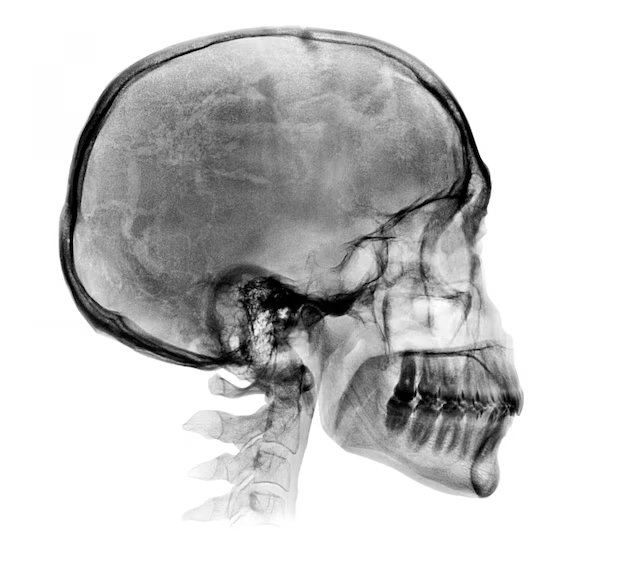

Cuando los médicos le realizaron una tomografía para ver si había un mal en su cabeza se llevaron una enorme sorpresa pues literalmente vieron que tenía una bala dentro del cráneo. Lo ingresaron de urgencia y extrajeron el proyectil al instante. Estuvo unos días en el hospital pues debían supervisar que todo estuviera bien y después de algunas semanas lo mandaron a su casa. Una vez en su hogar, se curó completamente y se quedó solo con una gran historia para contar

Las autoridades dijeron que nadie le había disparado directamente Facio, lo que ocurrió es que tuvo la mala fortuna de recibir el impacto de una bala perdida. El cirujano que atendió al joven también hizo un comunicado diciendo que sí la bala hubiera impactado a menos de 1 mm. de donde lo hizo, Facio hubiera sufrido una parálisis permanente de todo su lado derecho, pues la bala comprimía una terminación nerviosa encargada del movimiento.